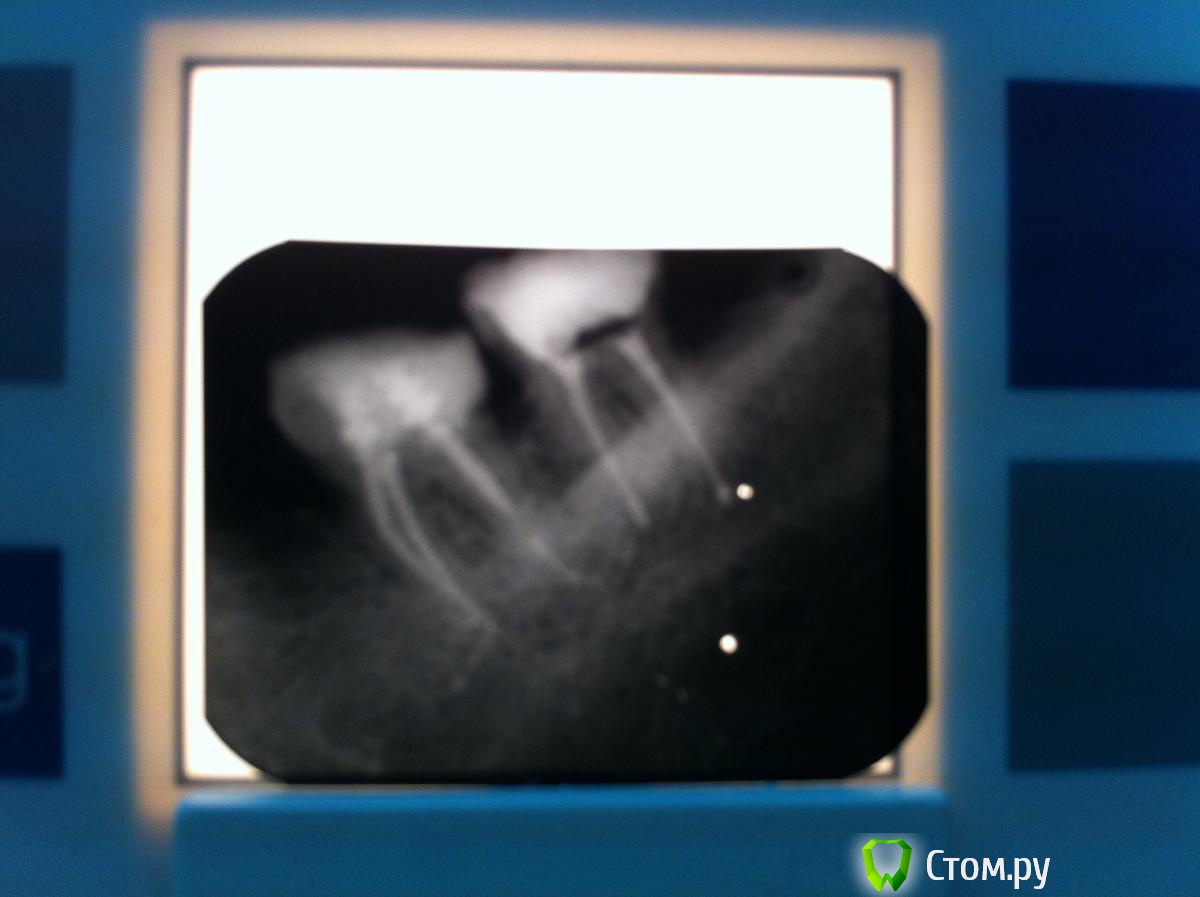

M@estro Опубликовано 1 декабря, 2013 Автор Поделиться Опубликовано 1 декабря, 2013 Недавно тема была про апексы, Гер Берра создавала, не в бровь - а в глаз : http://s020.radikal.ru/i723/1312/d9/13699f1a65de.jpg Зуб 2.6,4 месяца назад была попытка сохранения "витальности",вскрыт в 1 точке,закрыт мта, симтоматики никакой за неделю не проявилось,реставрировали. Пришел 2 недели назад - жалобы на боли (холодное) . Эод,депульпируем, в первое посещение - первичная обработка , кальций. Во второе посещение найден мб 2,патенси не получил,обработал на 17 миллиметров(мб1 21 мм), нёбный 26 мм Получил в нёбном "сюрприз" 9 Ссылка на комментарий